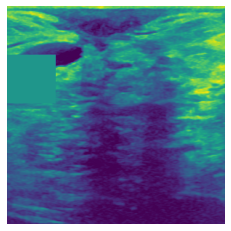

(a) Original

(b) Intelligent-Masking

(c) Context Prediction

(d) Context Restoration

Figure 3: More qualitative examples of different distorting strategies including our method. We show the different self-supervised mechanisms on both datasets of MR (rows: 1-3) and ultrasound (rows: 4-6) images for lower-grade glioma and breast cancer diagnosis respectively. We include both images of normal (rows: 1,4) and cancer (rows: 2,3,5,6) conditions for each dataset. We also observe that our method treats each image based on its context information with no predetermined strategy.